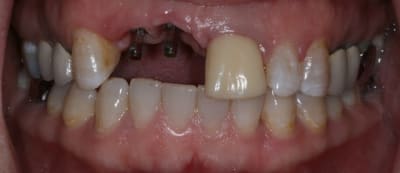

Patiente de 30 ans suite à parodontite a perdu 11-12 avec grosse perte osseuse.

J'ai suffisamment d'os pour prévoir la pose implantaire sans greffe mais esthétiquement je pense que cela va être moche car la ligne du sourire me semble bien haute.

Qu'en pensez vous ?

si tu implantes comme ça, on est bien d'accord que ça va être moche.

que comptes tu faire de la 21? as tu une rétro?

tu devrais faire faire par ton prothésiste un wax avec les dents en blanc et les tissus mous qu'il te manque en rouge afin de bien visualiser tous les tissus qu'il te manque.

il y a un truc qui me chiffonne, tu dis que cette patiente de 30 ans, a perdu ses deux ans suite a une parodontite?, mais alors vraiment très très localisée, car je ne vois aucun problème ailleurs

Peut elle te dire la cause exacte? ou est ce toi qui tenue par SP, dit n'importe quoi?

Bon ben j'ai implanté avant d'avoir refait la 21. Du coup j'ai mésialé la pose de 11 pour compenser la distalisation de 21.

Au final je n'ai pas fait de greffe osseuse... et j'ai réalisé une technique de rouleau sur 11-12 mais je reste un peu court à mon goût.

J'ai mis en place des transitoires sur 11-12-21 pour temporiser 3 mois pour voir la maturation des tissus mous.

La vraie difficulté a été de retrouver le milieu incisif pour déterminer la position des implants.